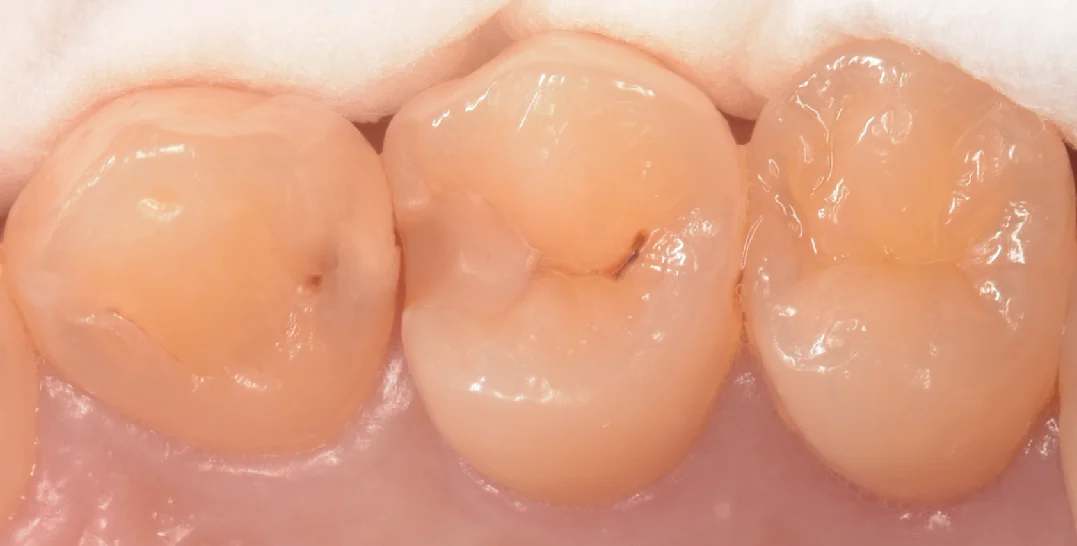

まずは術前からです。

画像上で左二つの治療を今回行いました。

真ん中は古いプラスチックが欠けていますがぱっと見はむし歯はなさそうに見えます。

対して左側の歯はどう見ても内部で大きくなってそうな、黒っぽいのが透けて見えている状態です。